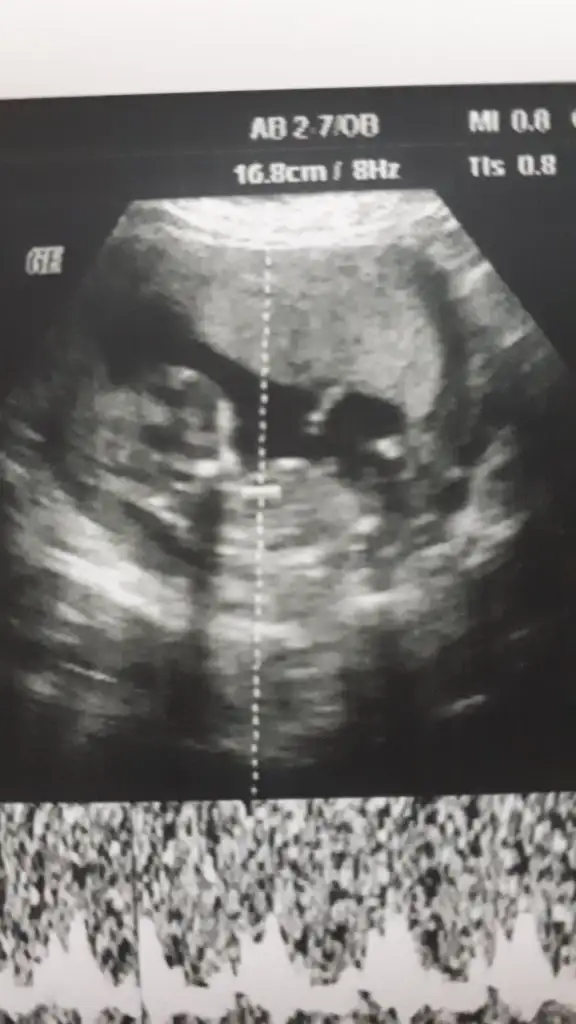

Merhaba arkadaşlar benim için de tahmin eder misniz ?

Eklentiler

• 20190805_121323.webp

Benim gibi ikili testte Dr .%70 kız dedi cumartesi başka Dr .gittim kız dedi sonra da inşallah yanilmam dedi .şimdi bebeğim kızdır dimi burdada herkes kız demişti 😊

Evet canım tam kesin değilmiş ama kıza benziyor dedi doktor. Kıpır kıpır göremiyorum dedi☺